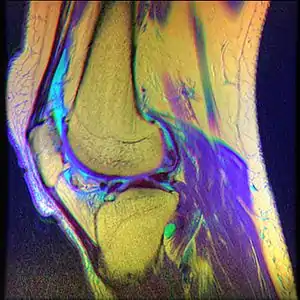

a,c,e) MRI scans consistent with chondromalacia patellae

• Magnetic Resonance Imaging (MRI) – to observe cartilage condition and assess deterioration